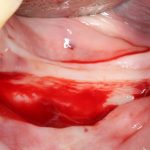

Вот клиническая картина через 4 месяца после ранее проведенной имплантации с остеопластикой:

Как видишь, коллеги из недалекой дружественной страны не осилили снятие швов. Мне это не нравится, хотя и объясняет, почему люди готовы ехать за тыщи километров ради 20-минутной операции удаления зуба мудрости.

Ну хорошо. Швы сняли. Делаем разрез. Обрати внимание, что после всех проведенных операций у нас остается очень небольшой по ширине слой жевательной слизистой оболочки: